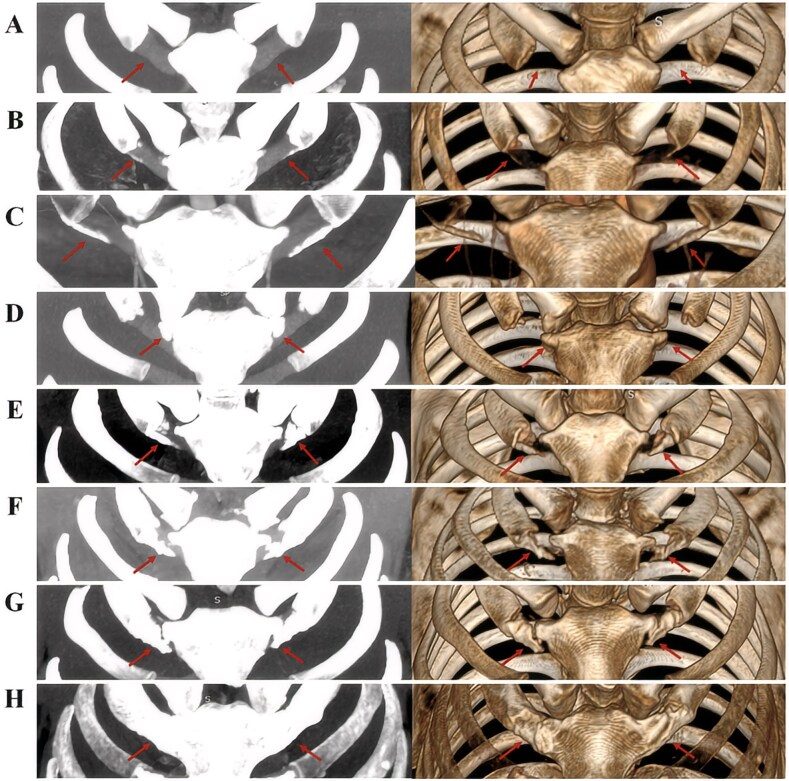

Age estimation of adults is a challenging procedure in forensic practice. Inspired by the previous work by Chinese scholars, we established population-specific age estimation models from the osseous and calcified projections (OCPs) of costal cartilages, using three-dimensional volume-rendering technique. A total of 168 clinical CT scans (2 mm slice thickness) were used to develop the sex-specific age prediction models from a sample of Egyptians, comprising 70 females and 98 males, with documented ages between 12 and 85 years. The sample was also used for validating the Chinese model. We reported the differences between the predictive accuracy of the Egyptian (population specific) and Chinese (non-population specific) models. The most accurate age estimation model was stepwise linear regression with standard error of estimates of 10.9 and 11.8 years in males and females, respectively. For the simple linear regression models, the most accurate formula included OCP of the right second costal cartilage in males and OCP of the left third costal cartilage in females with standard error of estimates of 11.2 and 12.2 years, respectively, and mean absolute error (MAE) of 8.8 and 9.6 years, respectively. By comparison, the best accuracy rates produced by the Chinese vs. the Egyptian models in males and females within 5 years were 30.61% and 32.86% vs. 35.71% and 32.86%, respectively, whereas within 10 years, the accuracy rates increased up to 57.14% and 58.57% vs. 72.45% and 64.29%, respectively. Although the accuracy rates from the Chinese models were lower than those obtained from the Egyptian models, the MAE and least error values were comparable in both sexes. Notable accurate age estimation rates in the advanced age group ≥40 years were reached being 81.25% to 97.92% in males and 69.77% to 93.02% in females. OCP of the right first costal cartilage was the most accurate in cross-population application for males and females with MAE values of 10.7 and 11.03 years, respectively, with balanced accuracy rates of age estimation using the 10-year interval and 40-year cutoff.

Key points: Age differences in calcification form and amount in the seven costal cartilages were found.The best model for males include the second costal cartilage.The best model for females include third or fifth costal cartilages.First OCP is the most accurate in cross-population application regardless of sex.The best OCP in one population is not necessarily the best predictor in both samples.